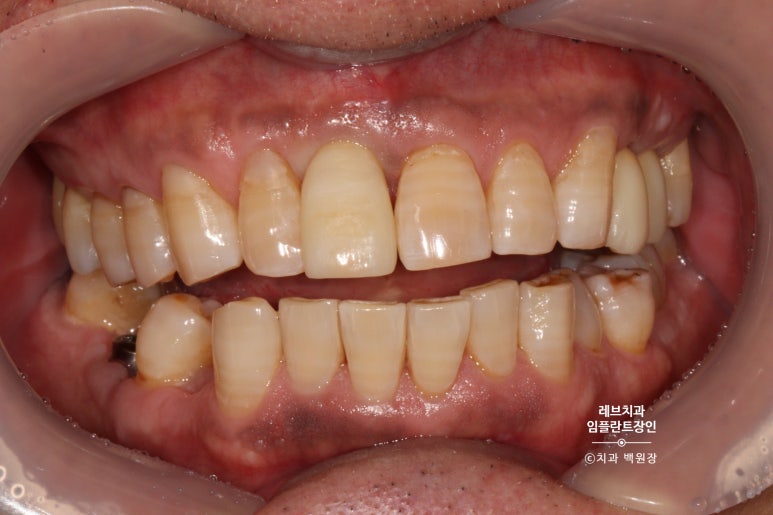

그리하여 유사하게 만들어본 앞니입니다.

왼쪽 위 작은 앞니와 송곳니를 합쳐서 2개짜리 보철물을 만들었어요!

완성 후 촬영한 치과용 방사선 엑스레이 사진에서도, 깔끔하게 완성된 보철물을 보실 수 있을겁니다.